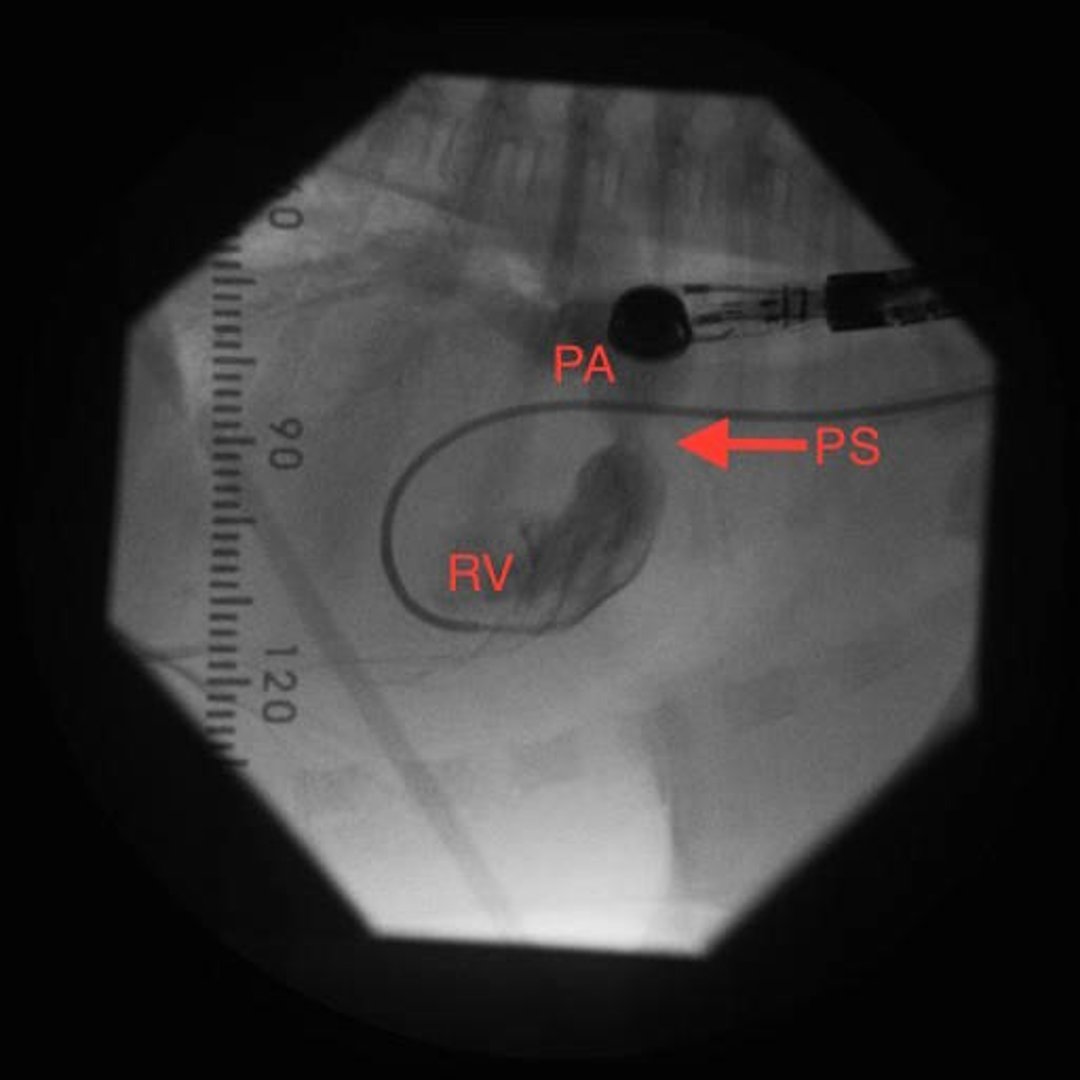

Estenosis pulmonar valvular, angiografía, perro

Angiografía de perro en decúbito lateral izquierdo. La inyección de material de contraste a través de un catéter en el ventrículo derecho muestra un realce del tracto de salida del ventrículo derecho y de la arteria pulmonar. Obsérvese un estrechamiento a nivel de las valvas de la válvula pulmonar, compatible con estenosis valvular pulmonar. PA, arteria pulmonar; PS: estenosis pulmonar; RV, ventrículo derecho.

Cortesía de la Dra. Sandra Tou.